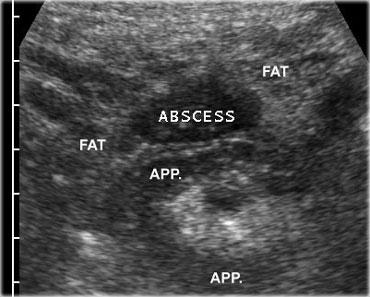

Viêm hồi tràng do Crohn với đường rò (mũi tên) vào ruột thừa lân cận. Lưu ý sự mất cấu trúc lớp khu trú của thành hồi tràng và các khối mỡ viêm xung quanh lớn (fat).

Trên siêu âm, thành hồi tràng dày lên rõ rệt, nhu động giảm hoặc mất hoàn toàn và không thể ép xẹp được.

Điển hình, tất cả các lớp thành ruột đều bị tổn thương và cấu trúc lớp thường bị phá vỡ khu trú, dấu hiệu sớm nhất là sự thay đổi giảm âm ở lớp dưới niêm mạc.

Có hiện tượng viêm mạc treo ruột và mạc nối, biểu hiện là mô tăng âm, không thể ép xẹp, nằm kề cận hồi tràng.

Trong lớp thành giảm âm, các tiêu điểm sáng lệch tâm có thể gợi ý loét sâu.

Các dải giảm âm trong mô tăng âm gợi ý các đường hoại tử mỡ, có thể là dấu hiệu báo trước của sự hình thành đường rò (Hình).